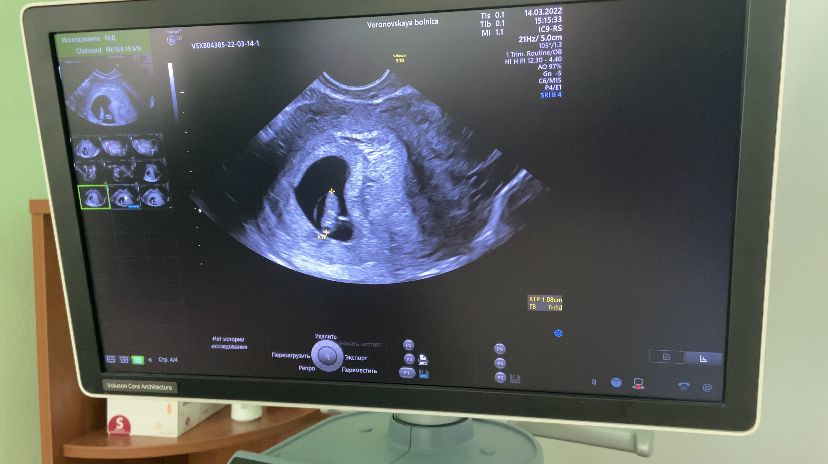

Узи на 7 неделе

Сходила уже на второе наше узи (первое было для определения маточной беременности),

по узи срок 7 недель и 1 день, по М - 6 недель 5 дней

сердечко бьется и все хорошо, готовимся к постановлению на учёт 🙏🏻